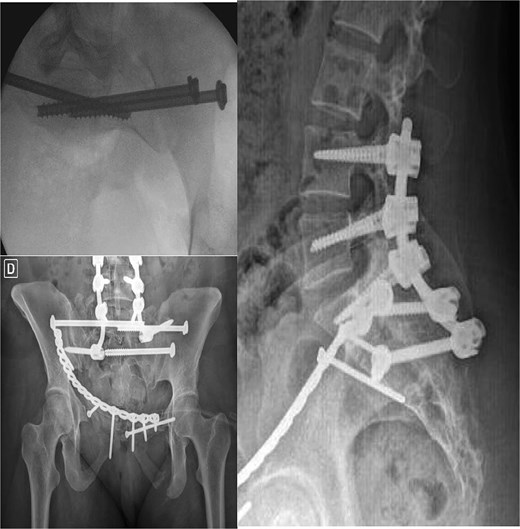

After one week of monitoring in the ICU, where she remained stable without need for ventilatory support, the patient was transferred to the ward. She then underwent the first surgical stage in supine position. Anterior pelvic fixation (Fig. 3a) was performed via a Pfannenstiel anterior approach combined with the first window of the right ilioinguinal approach, using a 3.5-mm reconstruction plate on the right anterior column crossing the pubic symphysis and a 3.5-mm retrograde screw in the left anterior column, inserted through the same Pfannenstiel access. During the same procedure, a 7.3-mm trans-sacral screw was placed in S1 on the right to stabilize the sacral fracture (Fig. 4). The surgery lasted ⁓3 h, and the patient was transferred to the semi-intensive care unit for postoperative monitoring.

The second surgical stage was performed under general anesthesia two weeks later, delayed by one week of hemodynamic monitoring and subsequent unavailability of surgical materials. In supine position, the left sacroiliac joint was fixed with two 7.3-mm cannulated screws, and a seroma in the Pfannenstiel approach was drained. Subsequently, with the patient repositioned in prone position (Fig. 3b), lumbopelvic fixation from L4-L5-S1 to the posterior ilium (EIPS) was performed using rods and pedicle screws (Fig. 5). This procedure lasted ⁓3 h. At this point, ˃3 weeks post-trauma, anatomical reduction was significantly hindered by early consolidation and fibrosis at the fracture sites, requiring extensive maneuvers. The patient was transferred to the ICU, extubated without complications the following day, and returned to the ward after two days, receiving hospital discharge thereafter.

The two-stage approach addressed initial severity (Fig. 3), using a Pfannenstiel and ilioinguinal approach for anterior fixation and an S1 trans-sacral screw for sacral stability [10, 11], followed by lumbopelvic fixation for posterior stability [12]. A 3-week delay, partly due to material unavailability, caused fibrosis, complicating reduction [13]. Seroma drainage in the second stage mitigated infection risks from the Pfannenstiel approach. ICU monitoring reflected management complexity despite stability [14]. Follow-ups over 18 months demonstrated functional recovery, quality-of-life gains, and psychological stability by 6 months, sustained to 18 months (Table 2, Fig. 7), despite early anxiety; this contrasts with studies linking severe psychological distress to poorer outcomes in Tile C fractures, suggesting early intervention mitigated these risks [5]. The Majeed score’s specificity, despite lacking a Portuguese version, and SF-12 supported outcomes analysis [15]. Pain assessment via the Numeric Pain Scale (NPS) revealed persistent lumbar pain radiating to right lower limb until the 4th week (NPS 4), resolving significantly by 3 months (NPS 1) and absent thereafter (Table 2, Fig. 7), consistent with rehabilitation progress and lumbopelvic fixation stability. This case underscores surgical timing challenges, the impact of delayed fixation, and multidisciplinary care’s value.